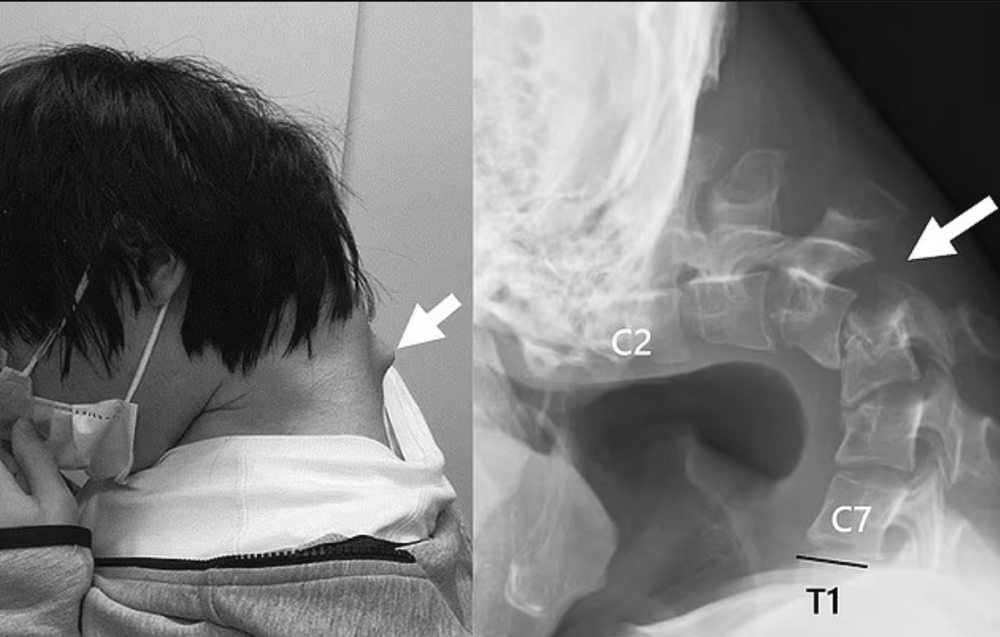

Однако, поскольку пациент жаловался на онемение при ношении устройств, данное лечение было прекращено. Решили проблему сурово, провели парочку операций, удалили лишнее, вкрутили ему в шею ряд винтов и металлических стержней, чтобы исправить осанку.

Через полгода пациент уже мог самостоятельно держать голову и нормально есть. С чем мы его от лица остальных геймеров и поздравляем.Спину выпрями и голову подними!